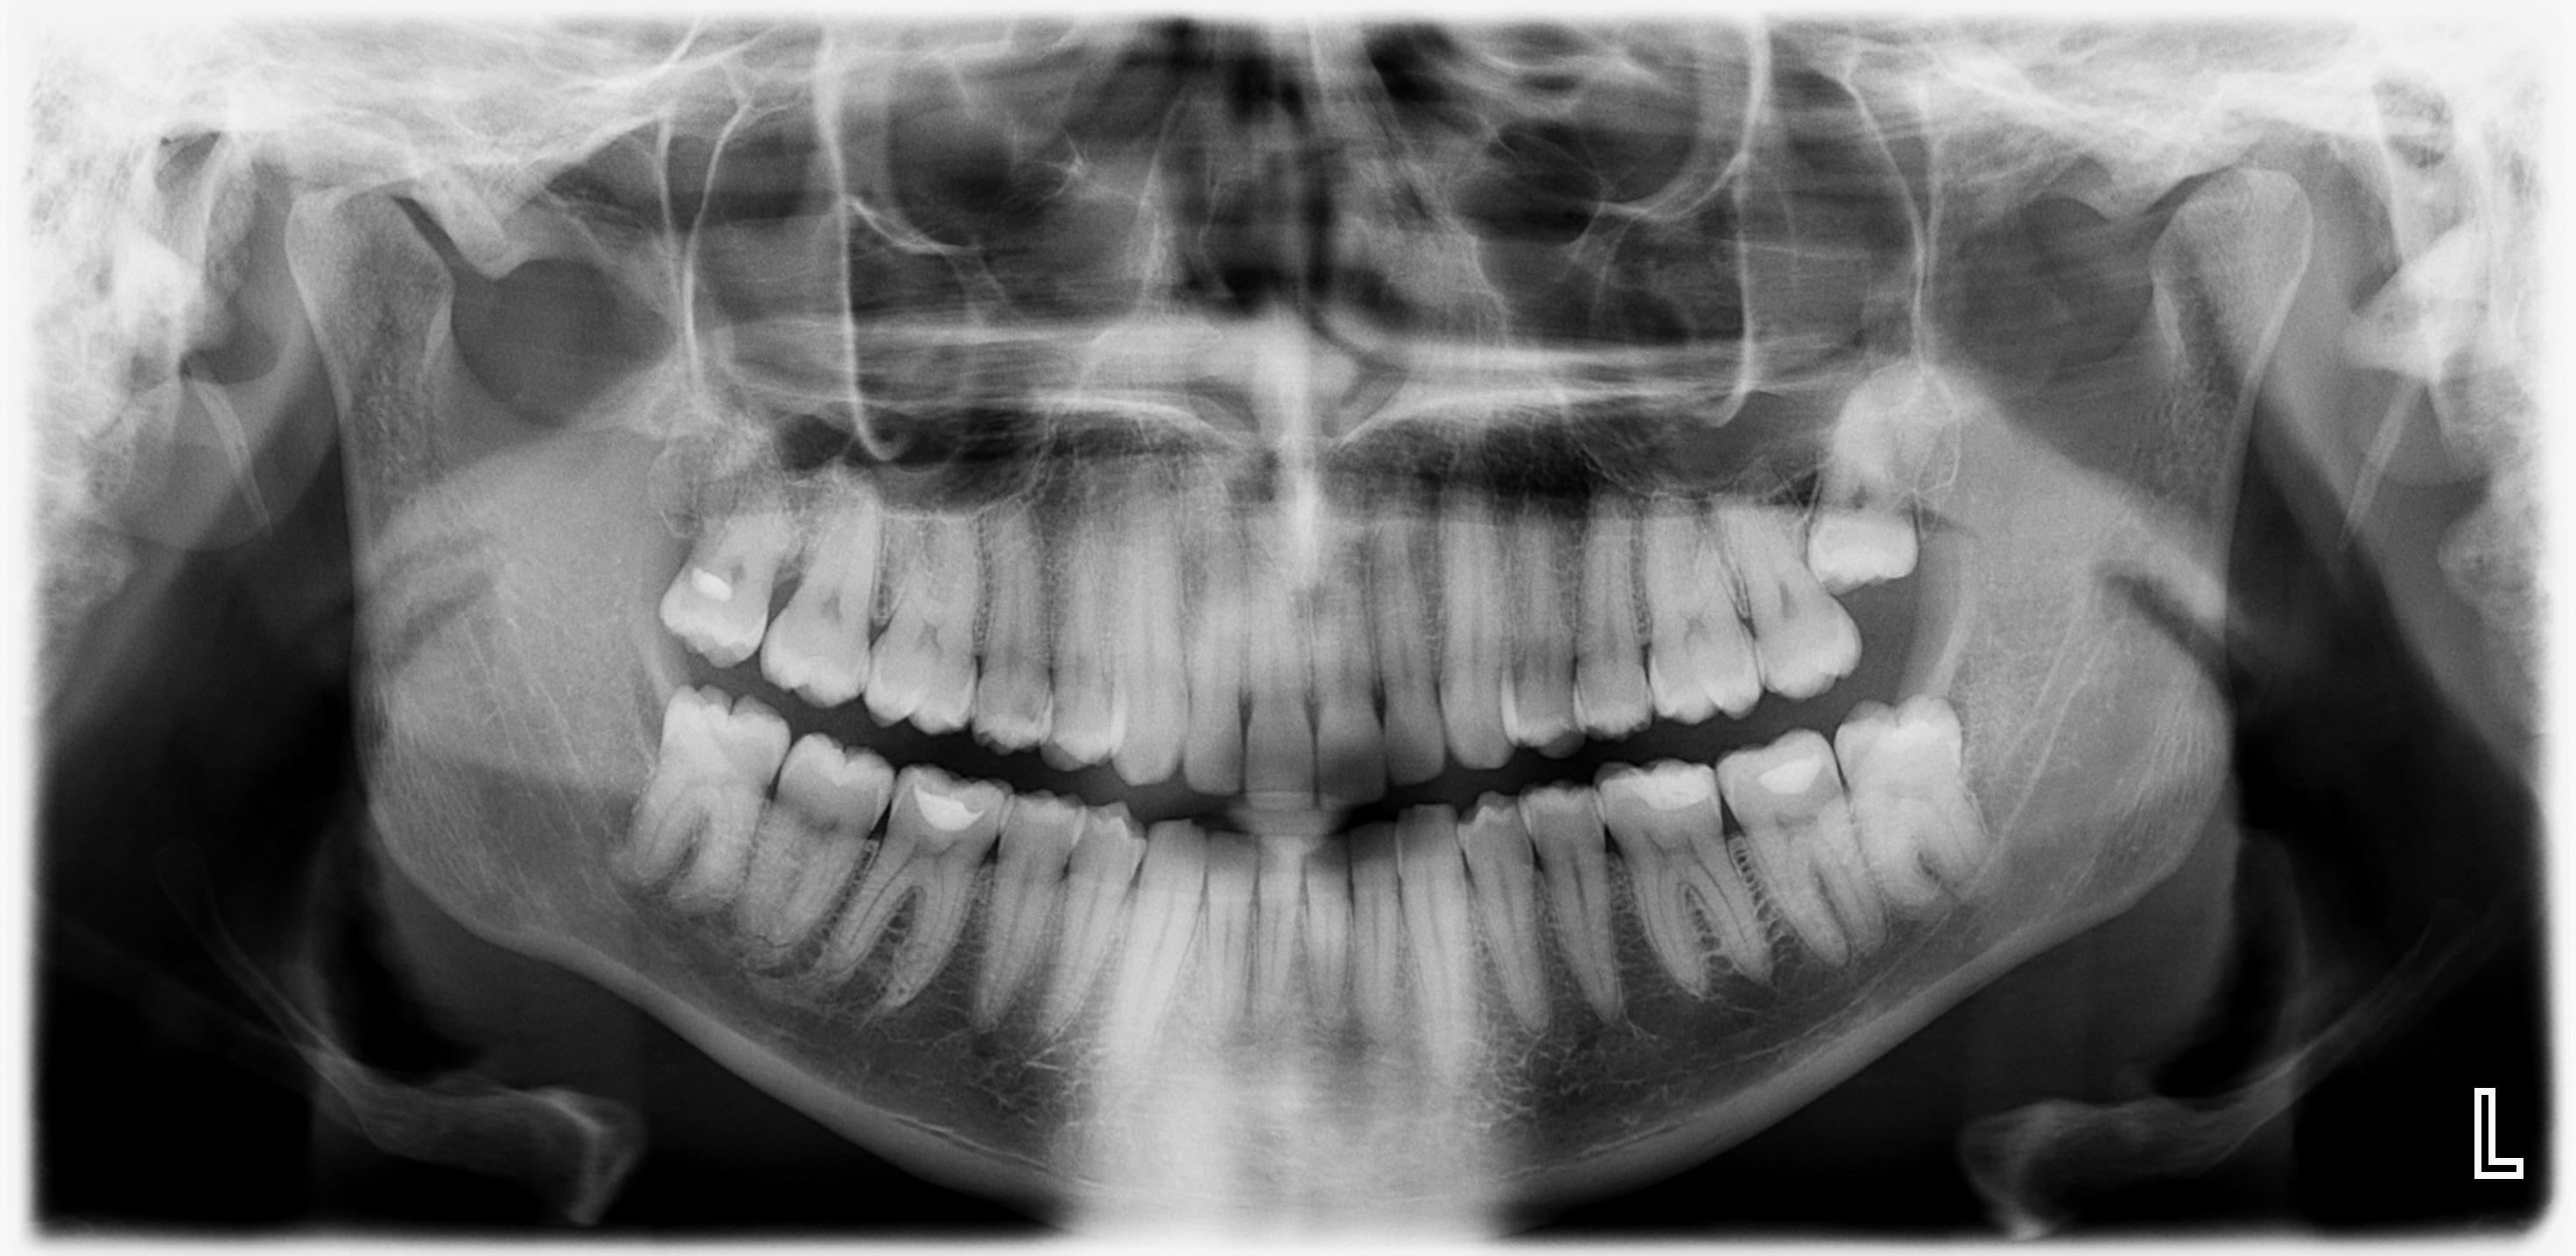

Experiencing lip numbness after wisdom teeth removal is common due to nerve trauma. Injury to the lingual nerve will affect sensations in the tissue lining the inside of the. Damage to the inferior alveolar nerve will cause sensation changes in the lower lip and chin. Numbness, tingling, or a lack of sensation in your mouth, cheeks, or face. While it's normal, persistent numbness could indicate a more serious issue. Lip numbness is rare, but it's possible. One potential side effect of wisdom tooth removal is numbness, which can occur in the tongue, lips, or cheeks. Consult your dentist if symptoms persist beyond a few days. Your wisdom teeth are close to the inferior alveolar nerve in the jaw. If you experience severe pain or excessive bleeding,.

My Bottom Lip Is Numb After Wisdom Tooth Extraction